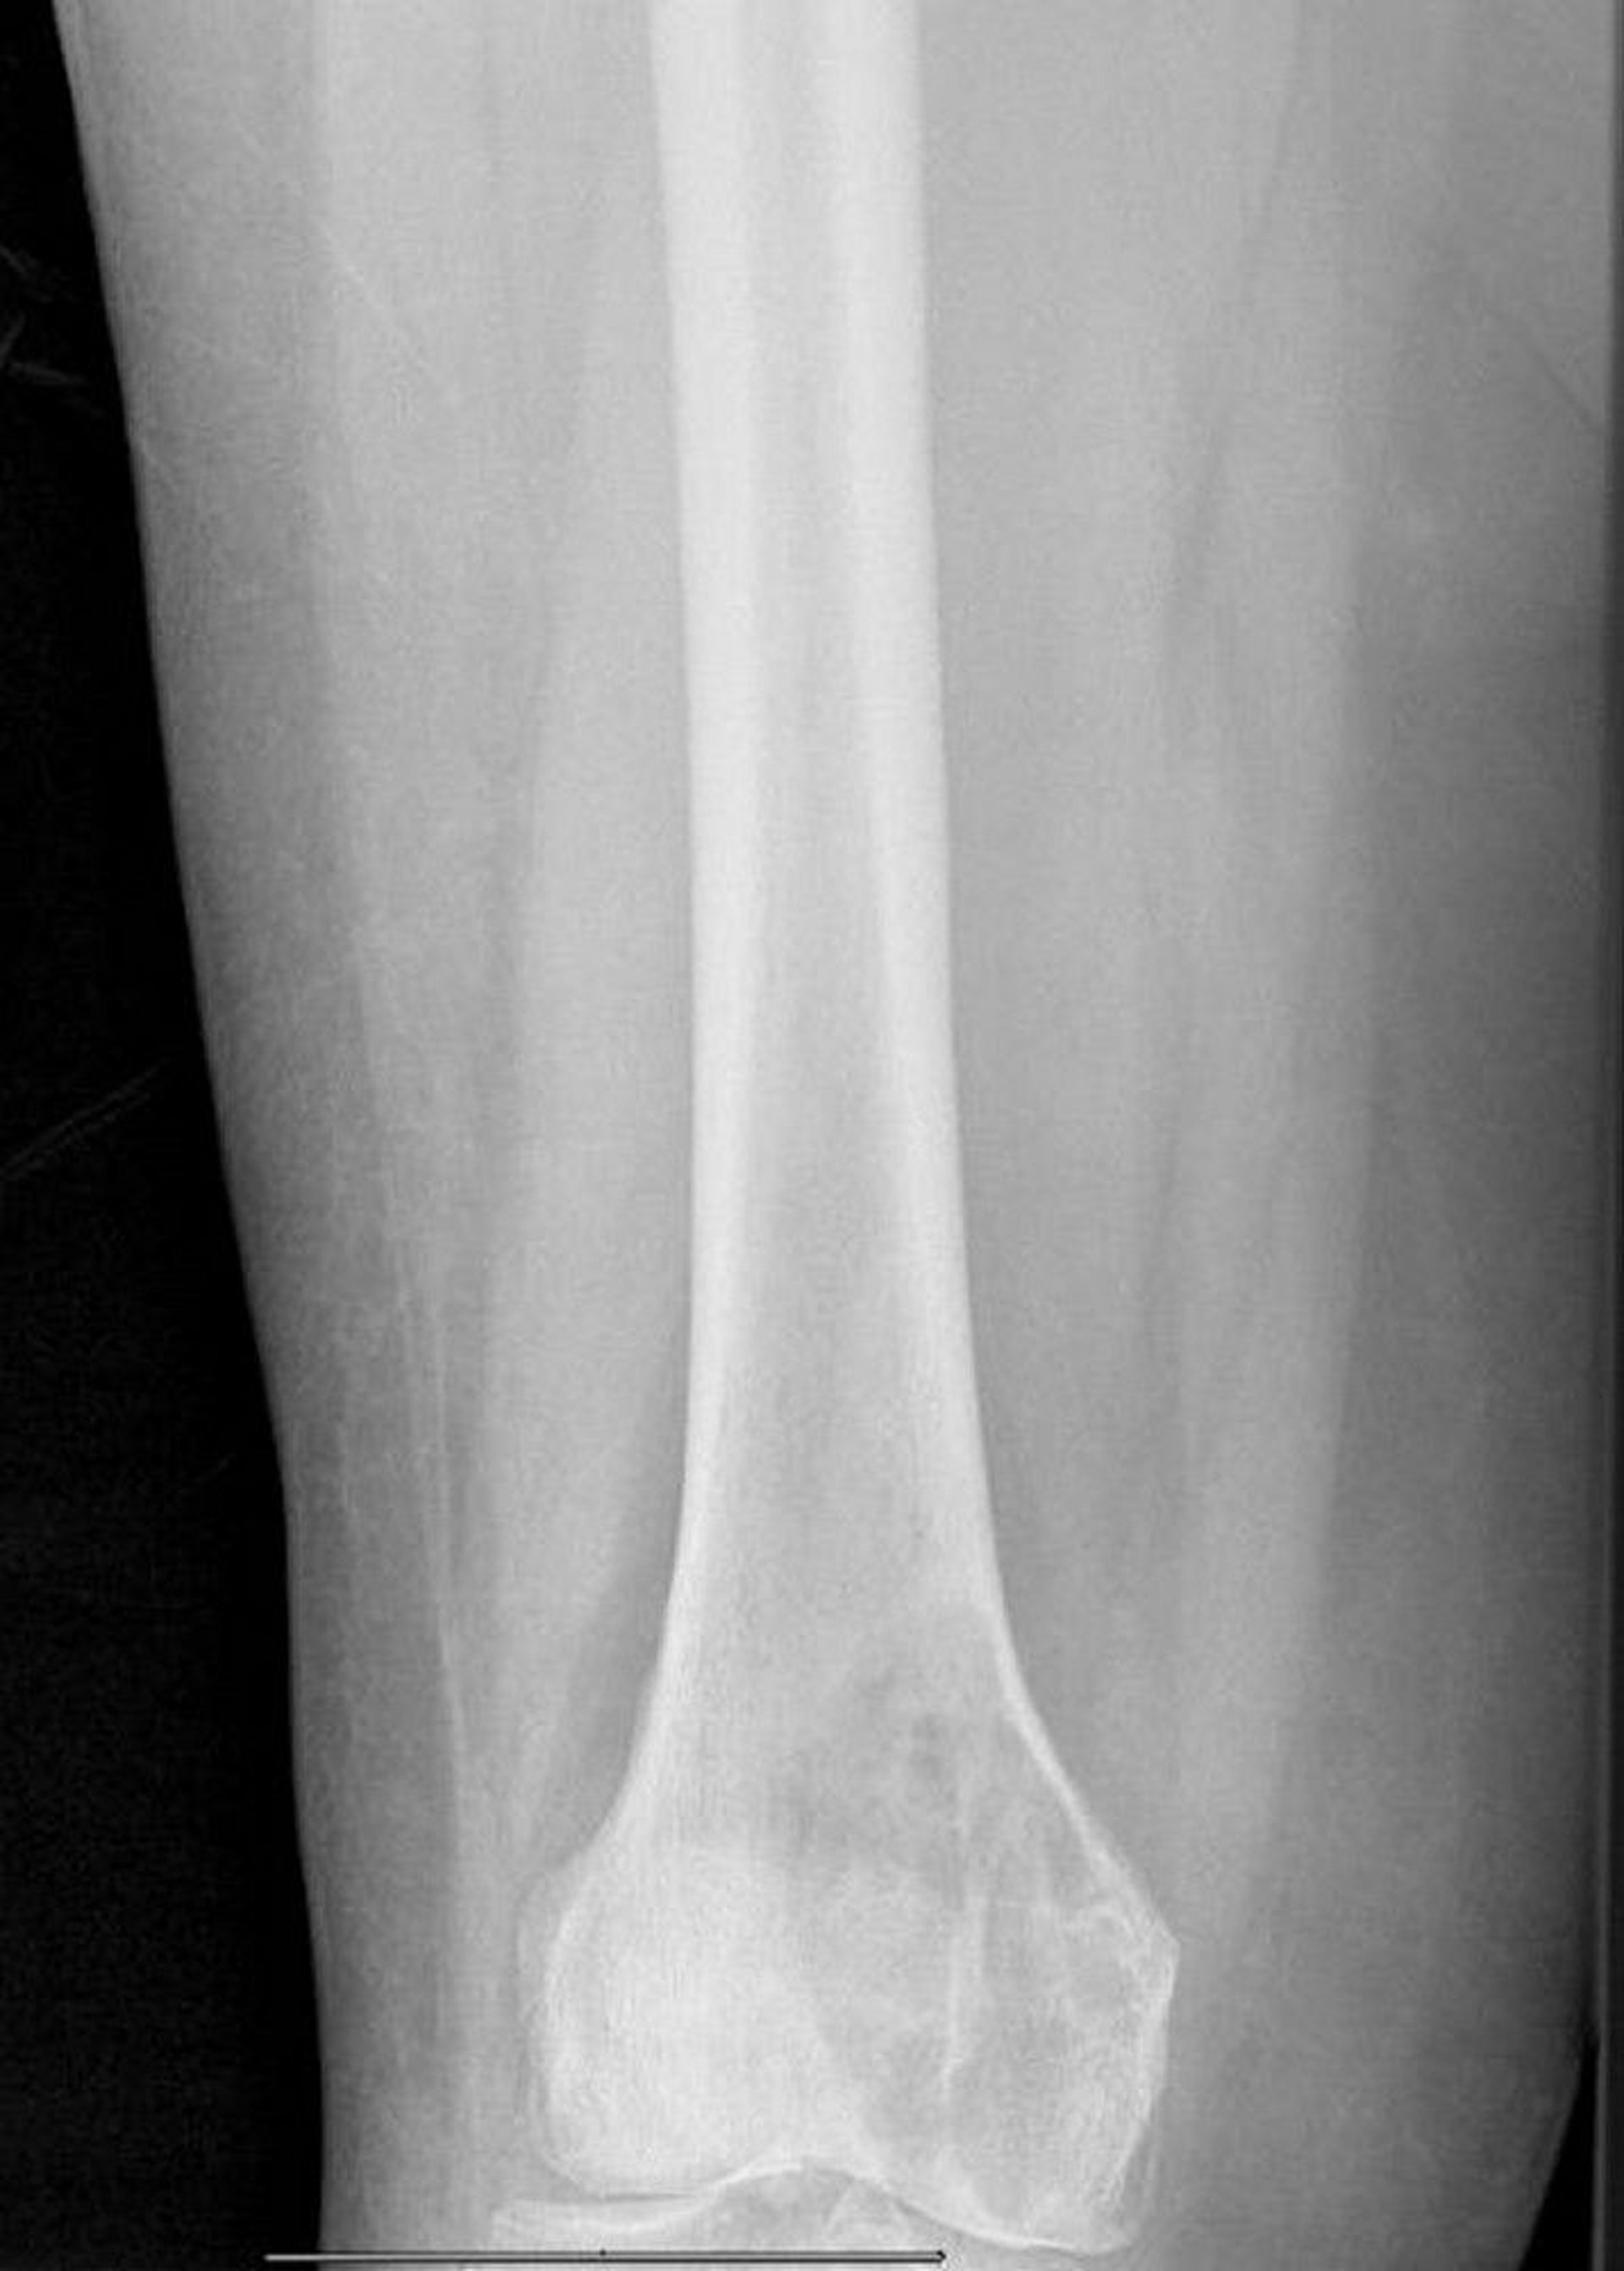

このX線写真には,大腿骨内顆に生じて切迫骨折の状態にある溶骨性の大きな転移性病変が写っている。

Image courtesy of Michael J.Joyce, MD, and David M.Joyce, MD.